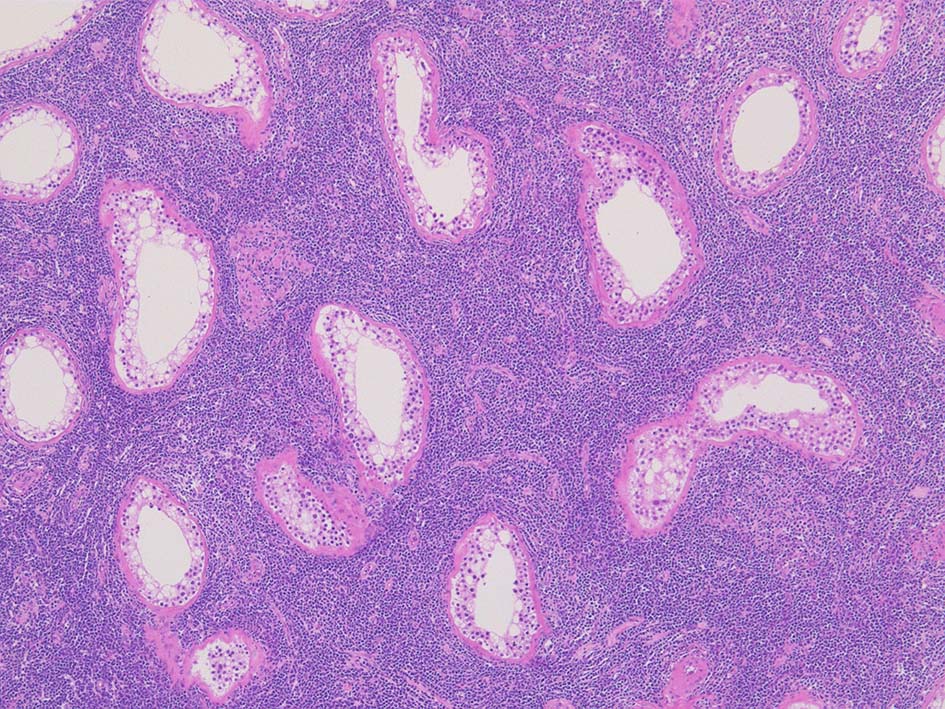

光顕所見; リンパ腫により, 少なくとも一部の領域の精細管が消失する. 末梢の領域では精細管の間質にリンパ腫細胞が浸潤する. ほとんどの場合、腫瘍細胞は精細管に侵入, 精細管の周辺を占め、生殖細胞とセルトリ細胞を中央に変位させるか, または精細管を完全に占拠してしまう.

増殖巣では精細管は消失, 萎縮. 腫瘍境界部での浸潤所見がある.

精細管の多くがスペアされ, 間質にlymphoid cellsが密に浸潤している. わずかな精細管に浸潤が認められ萎縮や破壊像が認められる. 精細管において Lymphoepithelial lesion(LEL)に似た所見がある.